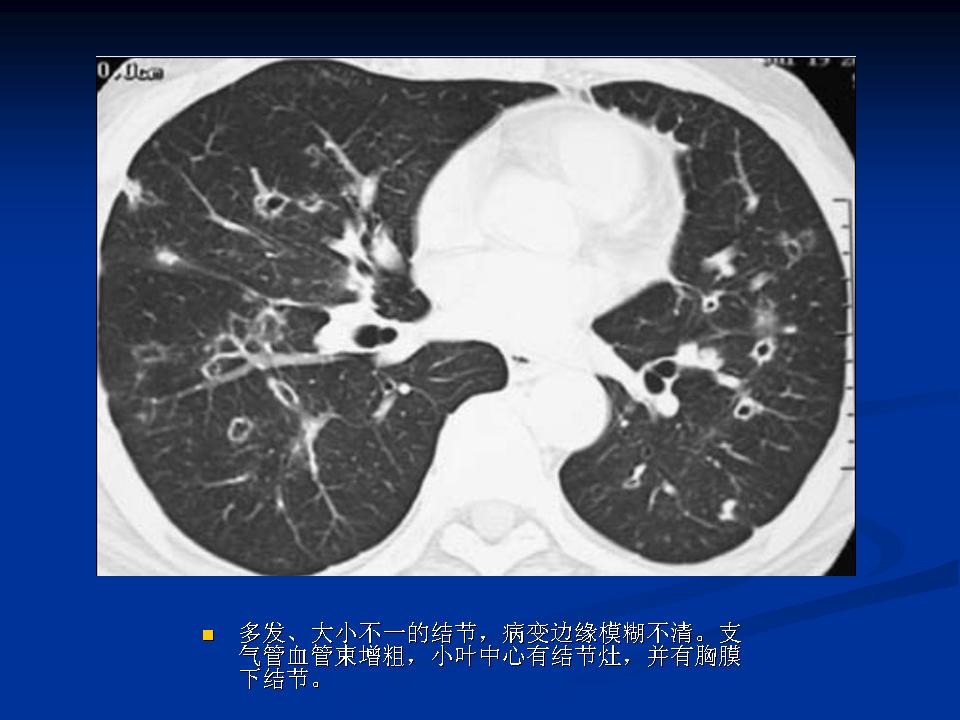

肺转移瘤与韦格肉芽肿影像鉴别